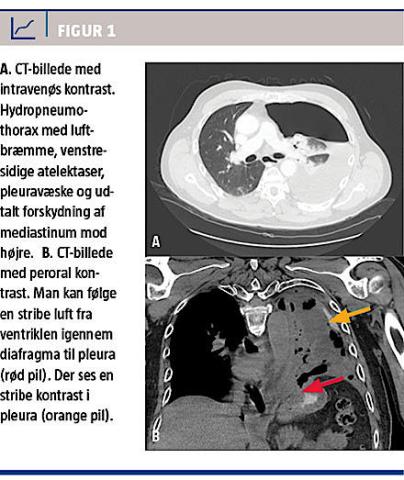

Der blev foretaget CT, som viste hydropneumothorax (Figur 1A) Der kunne ikke påvises nogen akut patologi abdominalt. Hydropneumothoraxen blev behandlet med anlæggelse af pleuradræn, der producerede luft og blodig væske.

Til trods for velfungerende dræn og antibiotisk trestofbehandling steg patientens infektionstal. På tredjedagen for indlæggelsen blev patienten diagnosticeret med pyopneumothorax sinister. Cytologisvar på pleuravæsken viste fremmedlegemer, som havde karakter af føderester, hvorfor patienten på fjerdedagen blev overflyttet til thoraxkirurgisk afdeling på mistanke om øsofagusperforation. Han fik foretaget en ny CT med peroral kontrast (Figur 1B). Denne verificerede mistanken om perforation, da der blev påvist kontrast i pleurahulen. Ved første gennemgang af skanningen kunne det ikke konstateres, hvor perforationen var.